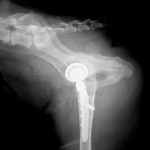

45kgの大型犬が股関節形成不全による痛みがあるとの事。他県より紹介来院されました。KyonのTHRシステム(人工関節)で傷んだ関節を置換しました。関節炎による痛みを感じるのは人も動物も同じです。出来るだけ痛みのない生活を過ごしてもらいたいと思います。インプラントはCup AOL 42° Large STEM 17°、Head19mm、Neck S、29.5 、Cup Anteversion 30°で埋入されています。内科治療に反応のない骨関節炎には人工関節で対応する事も可能です。しばらくは安静が必要です。